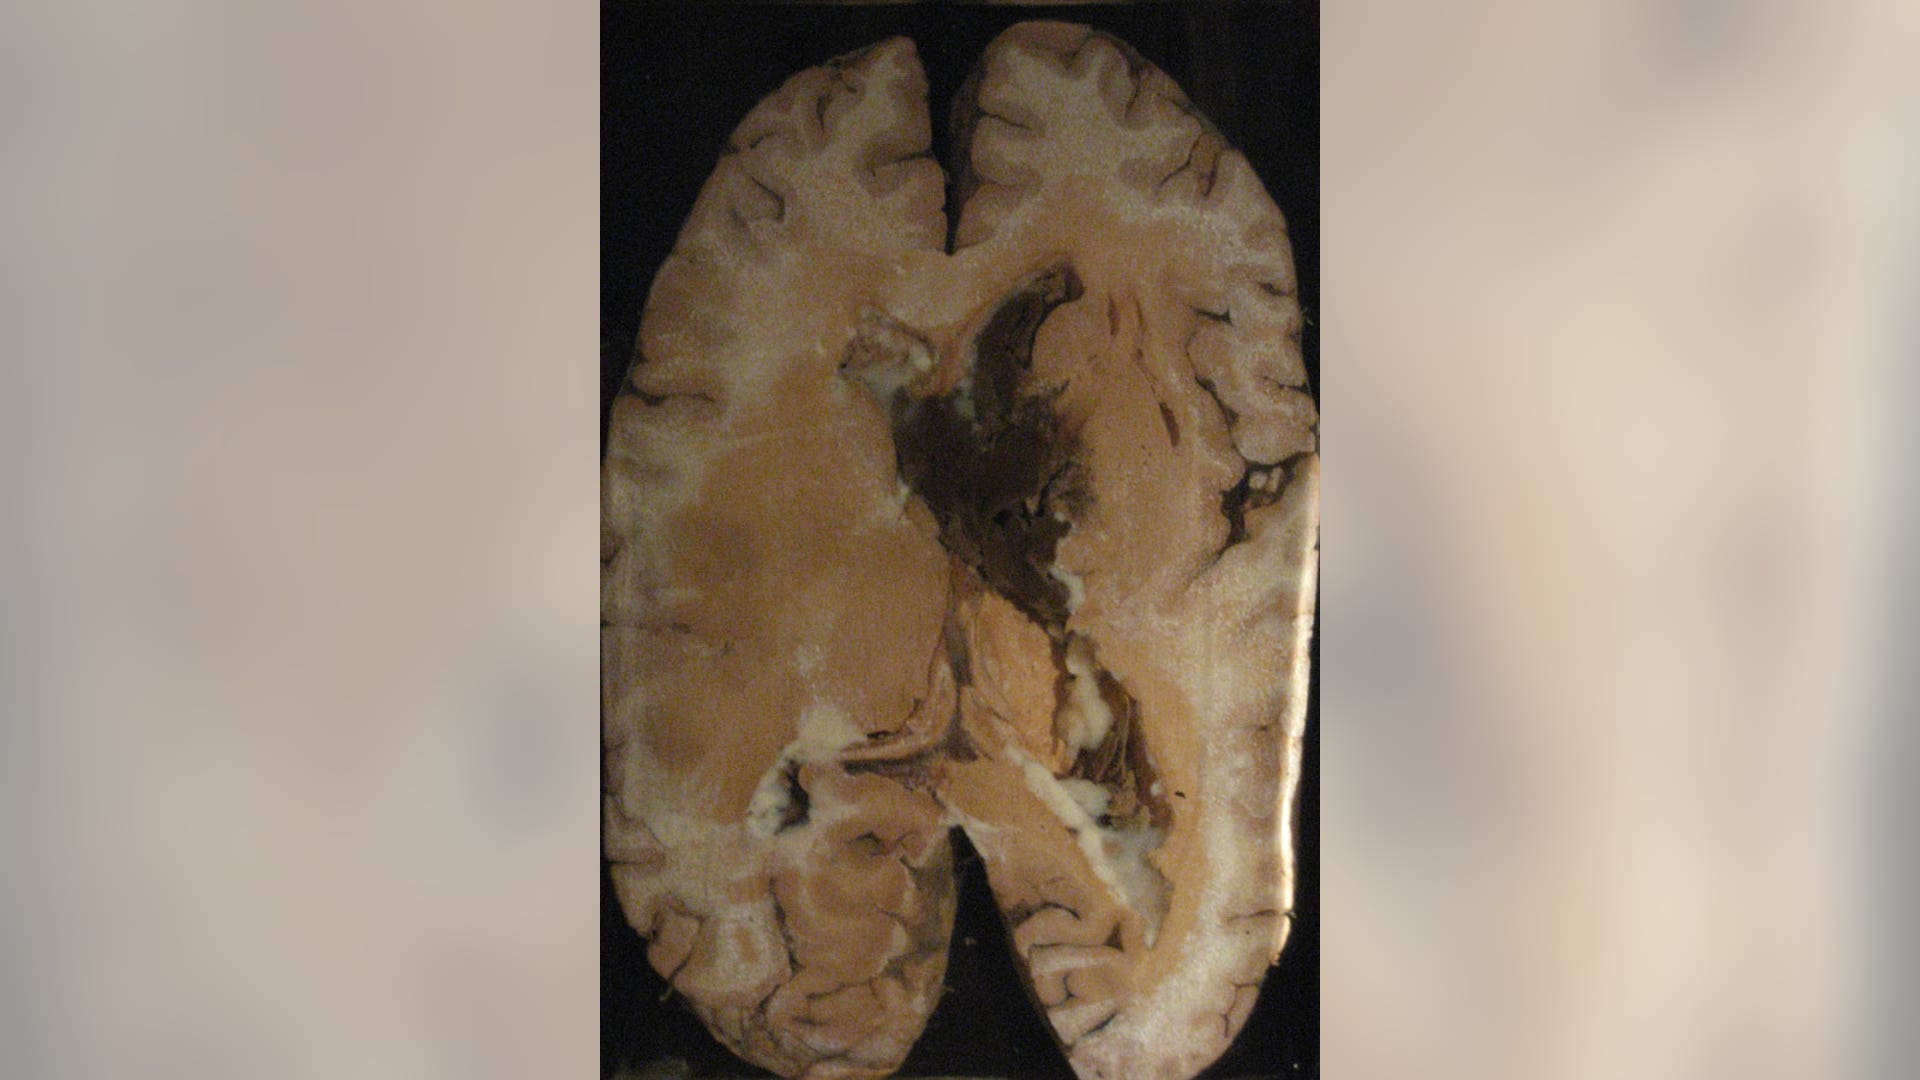

![Brain Hemorrhage]()